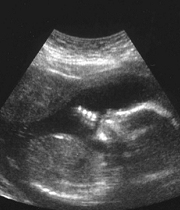

La revista de la Asociación Médica de Canadá señaló que los doctores no deberían revelar el sexo del feto hasta las 30 semanas de embarazo para evitar el aborto de niñas.

En su último número, la revista señala que Canadá se ha convertido en "un paraíso" para los padres que desean abortar los fetos femeninos, por su predilección por tener hijos varones.

Los datos del artículo señalan que la tasa natural de nacimientos entre varones y mujeres es de 1,05. Es decir, por cada 100 niñas nacen 105 niños.

La publicación indica que la tasa de nacimientos de varones en el primer bebé nacido de parejas de inmigrantes asiáticos que residen en Canadá es sólo ligeramente superior a esa cifra, específicamente de 1,08.